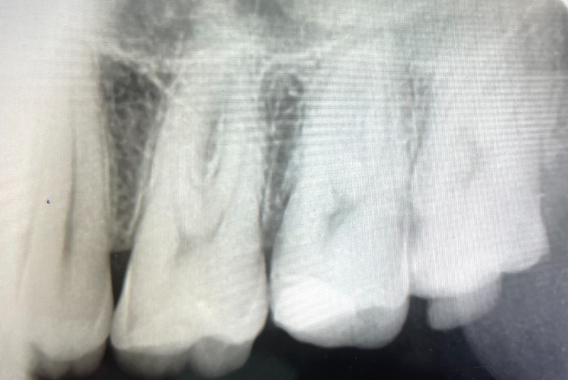

La endodoncia es la solución para conservar dientes que han sido afectados por caries profundas o trauma, eliminando el tejido dañado y protegiendo la estructura dental.

En AIEN, realizamos endodoncias utilizando lo último en tecnología radiográfica y tomografía, asegurando tratamientos eficientes y precisos que mantienen tus dientes funcionales y sin dolor